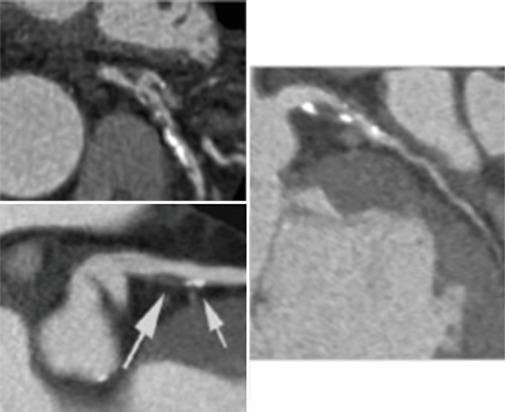

Cardiovascular diseases (CVDs) remain the leading cause of morbidity and mortality worldwide, and traditional preventive measures focus on lifestyle modifications, pharmacologic interventions, and risk stratification. Recently, imaging has emerged as an interesting tool in cardiovascular prevention. This review explores the role of various imaging modalities in early detection, risk assessment, and disease monitoring. Noninvasive techniques such as carotid ultrasound, arterial stiffness assessment, echocardiography, and coronary artery calcium scoring enable the identification of subclinical atherosclerosis and ventricular dysfunction, providing insights that complement conventional risk factors. Coronary computed tomography angiography and cardiac magnetic resonance offer high-resolution visualization of vascular and myocardial pathology, contributing to refined risk stratification. Furthermore, emerging markers such as epicardial adipose tissue and hepatic steatosis are gaining recognition as potential predictors of cardiovascular risk. Advancements in artificial intelligence (AI) are revolutionizing cardiovascular imaging by enhancing image interpretation, automating risk prediction, and facilitating personalized medicine. Future research should focus on optimizing the integration of imaging into clinical workflows, improving risk prediction models, and exploring AI-driven innovations. By exploiting imaging technologies, clinicians could enhance primary and secondary prevention strategies, ultimately reducing the global burden of CVDs.

心血管疾病(CVDs)仍然是全球发病和死亡的主要原因,传统的预防措施集中在生活方式改变、药物干预和风险分层上。最近,影像学已成为心血管预防领域一项引人关注的工具。本综述探讨了各种影像学检查方法在早期检测、风险评估和疾病监测中的作用。诸如颈动脉超声、动脉僵硬度评估、超声心动图和冠状动脉钙化积分等非侵入性技术能够识别亚临床动脉粥样硬化和心室功能障碍,提供补充传统危险因素的见解。冠状动脉计算机断层扫描血管造影和心脏磁共振成像能够对血管和心肌病变进行高分辨率可视化,有助于更精确的风险分层。此外,诸如心外膜脂肪组织和肝脂肪变性等新兴标志物正逐渐被认可为心血管风险的潜在预测指标。人工智能(AI)的进步正在通过增强图像解读、自动化风险预测和推动个性化医疗来彻底改变心血管成像。未来的研究应聚焦于优化影像学在临床工作流程中的整合、改进风险预测模型以及探索人工智能驱动的创新。通过利用成像技术,临床医生可以加强一级和二级预防策略,最终减轻全球心血管疾病负担。